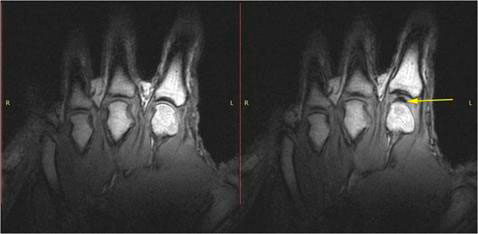

Si la causa se debe a un cartílago desgastado, la crepitación es consecuencia del roce interóseo, como el caso de la osteoartritis (artrosis) y el ruido es más común en la rodilla y en el cuello y además, puede progresar. La integridad articular depende en gran parte de la distribución de las fuerzas que soporta, por tanto, una alineación correcta es esencial para su buen funcionamiento. Las anormalidades de esta alineación (por traumatismo, lesión o déficit de fuerza de los músculos que se implican en su sostén) predisponen a la aparición de este tipo de enfermedad.